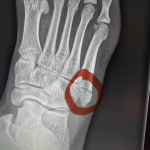

マネル・ケイプ、練習中に自爆骨折

この写真の記事へ